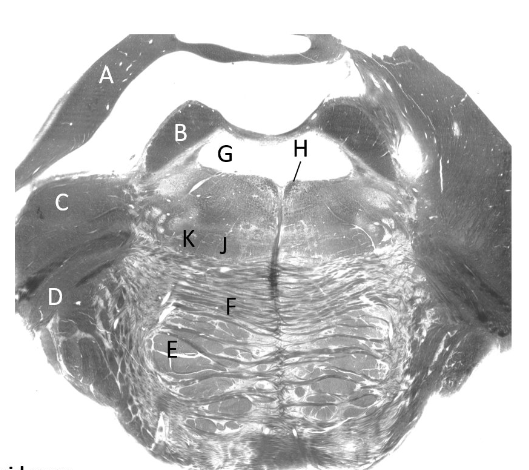

at what level is this?

lower medulla

what is a?

pyramid/ pyramidal tract (lm)

what is b?

spinal trigeminal nucleus (lm)

what is c?

trigeminal tract (lm)

what is d?

nucleus gracilis

what is e?

nucleus cuneatus (LM)

what is f?

internal arcuate fibres

what is g?

medial lemniscus (lm)

what is h?

inferior olivary nucleus (lm)